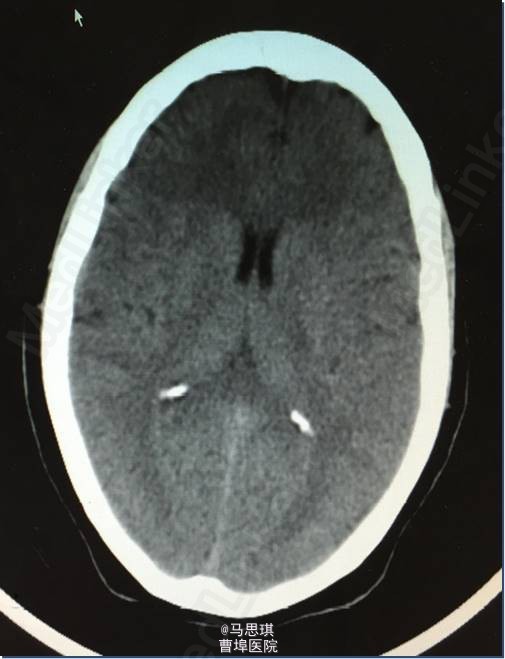

入院诊断为:“脑梗塞?” 患者有溶栓指征,但患者家属拒绝溶栓。 治疗: 氯吡格雷75mg Qd 拜阿司匹林0.1 Qd 立普妥 20mg qd 胞磷胆碱0.2tid 依达拉奉30mg ivgtt bid 康复治疗 入院第二天行MRI及MRA检查。 头部MRI:左侧额颞岛叶见片状稍长T2稍长T1信号灶,其内见较多增粗、增多血管影,原因?考虑:血管畸形所致左侧额颞岛叶缺血梗塞性改变?血管炎性病变或脑炎待排? 头颅MRA:左侧额颞岛叶见较多增粗、增多的血管影,右侧额颞顶交界区血管影稍增多。左侧胚胎型大脑后动脉。 入院第四天行头颅增强CT及CTA。 头颅增强CT:左侧颞叶见片状低密度影,其内见大小约0.7x1.6cm片状高密度影,与前片比较,见范围加大,考虑系梗塞后伴出血,血管畸形。增强扫描见左侧额颞叶较多迂曲扩张的血管影。 CTA:左侧额颞岛叶区域见大脑中动脉岛叶段,侧裂段及分叉段分支明显增多,部分迂曲、扩张,呈杂乱走行的血管团样改变,考虑血管畸形可能;右侧额顶交界区血管影稍增多。双侧颈内和基底动脉及大脑前中后动脉显示清晰,其大小、走行、信号未见确切异常,各血管壁光整,管腔未见确切狭窄,走行自然。 发现出血后,停用双联抗小板治疗,并加做DSA DSA示:左侧颈外动脉分支脑膜中动脉血管畸形,与颈内动脉,椎动脉无明显交通 修正诊断为: 左侧额颞岛叶脑梗塞并梗塞后出血; 左侧脑膜中动脉血管畸形 动脉粥样硬化症 上呼吸道感染

复查CT(3周后):左侧额颞顶叶片状脑梗塞密度较前片略降低。 3周后,患者行左侧脑膜中动脉血管畸形栓塞术,但因患者于部分供血血管造影时述左耳疼痛明显,放弃有明显临床症状供血血管栓塞术,随后出院。嘱氯吡格雷75mg Qd 立普妥 20mg qd 讨论:对于此类特殊病因的卒中患者如何评估溶栓风险?如何评估双抗风险?